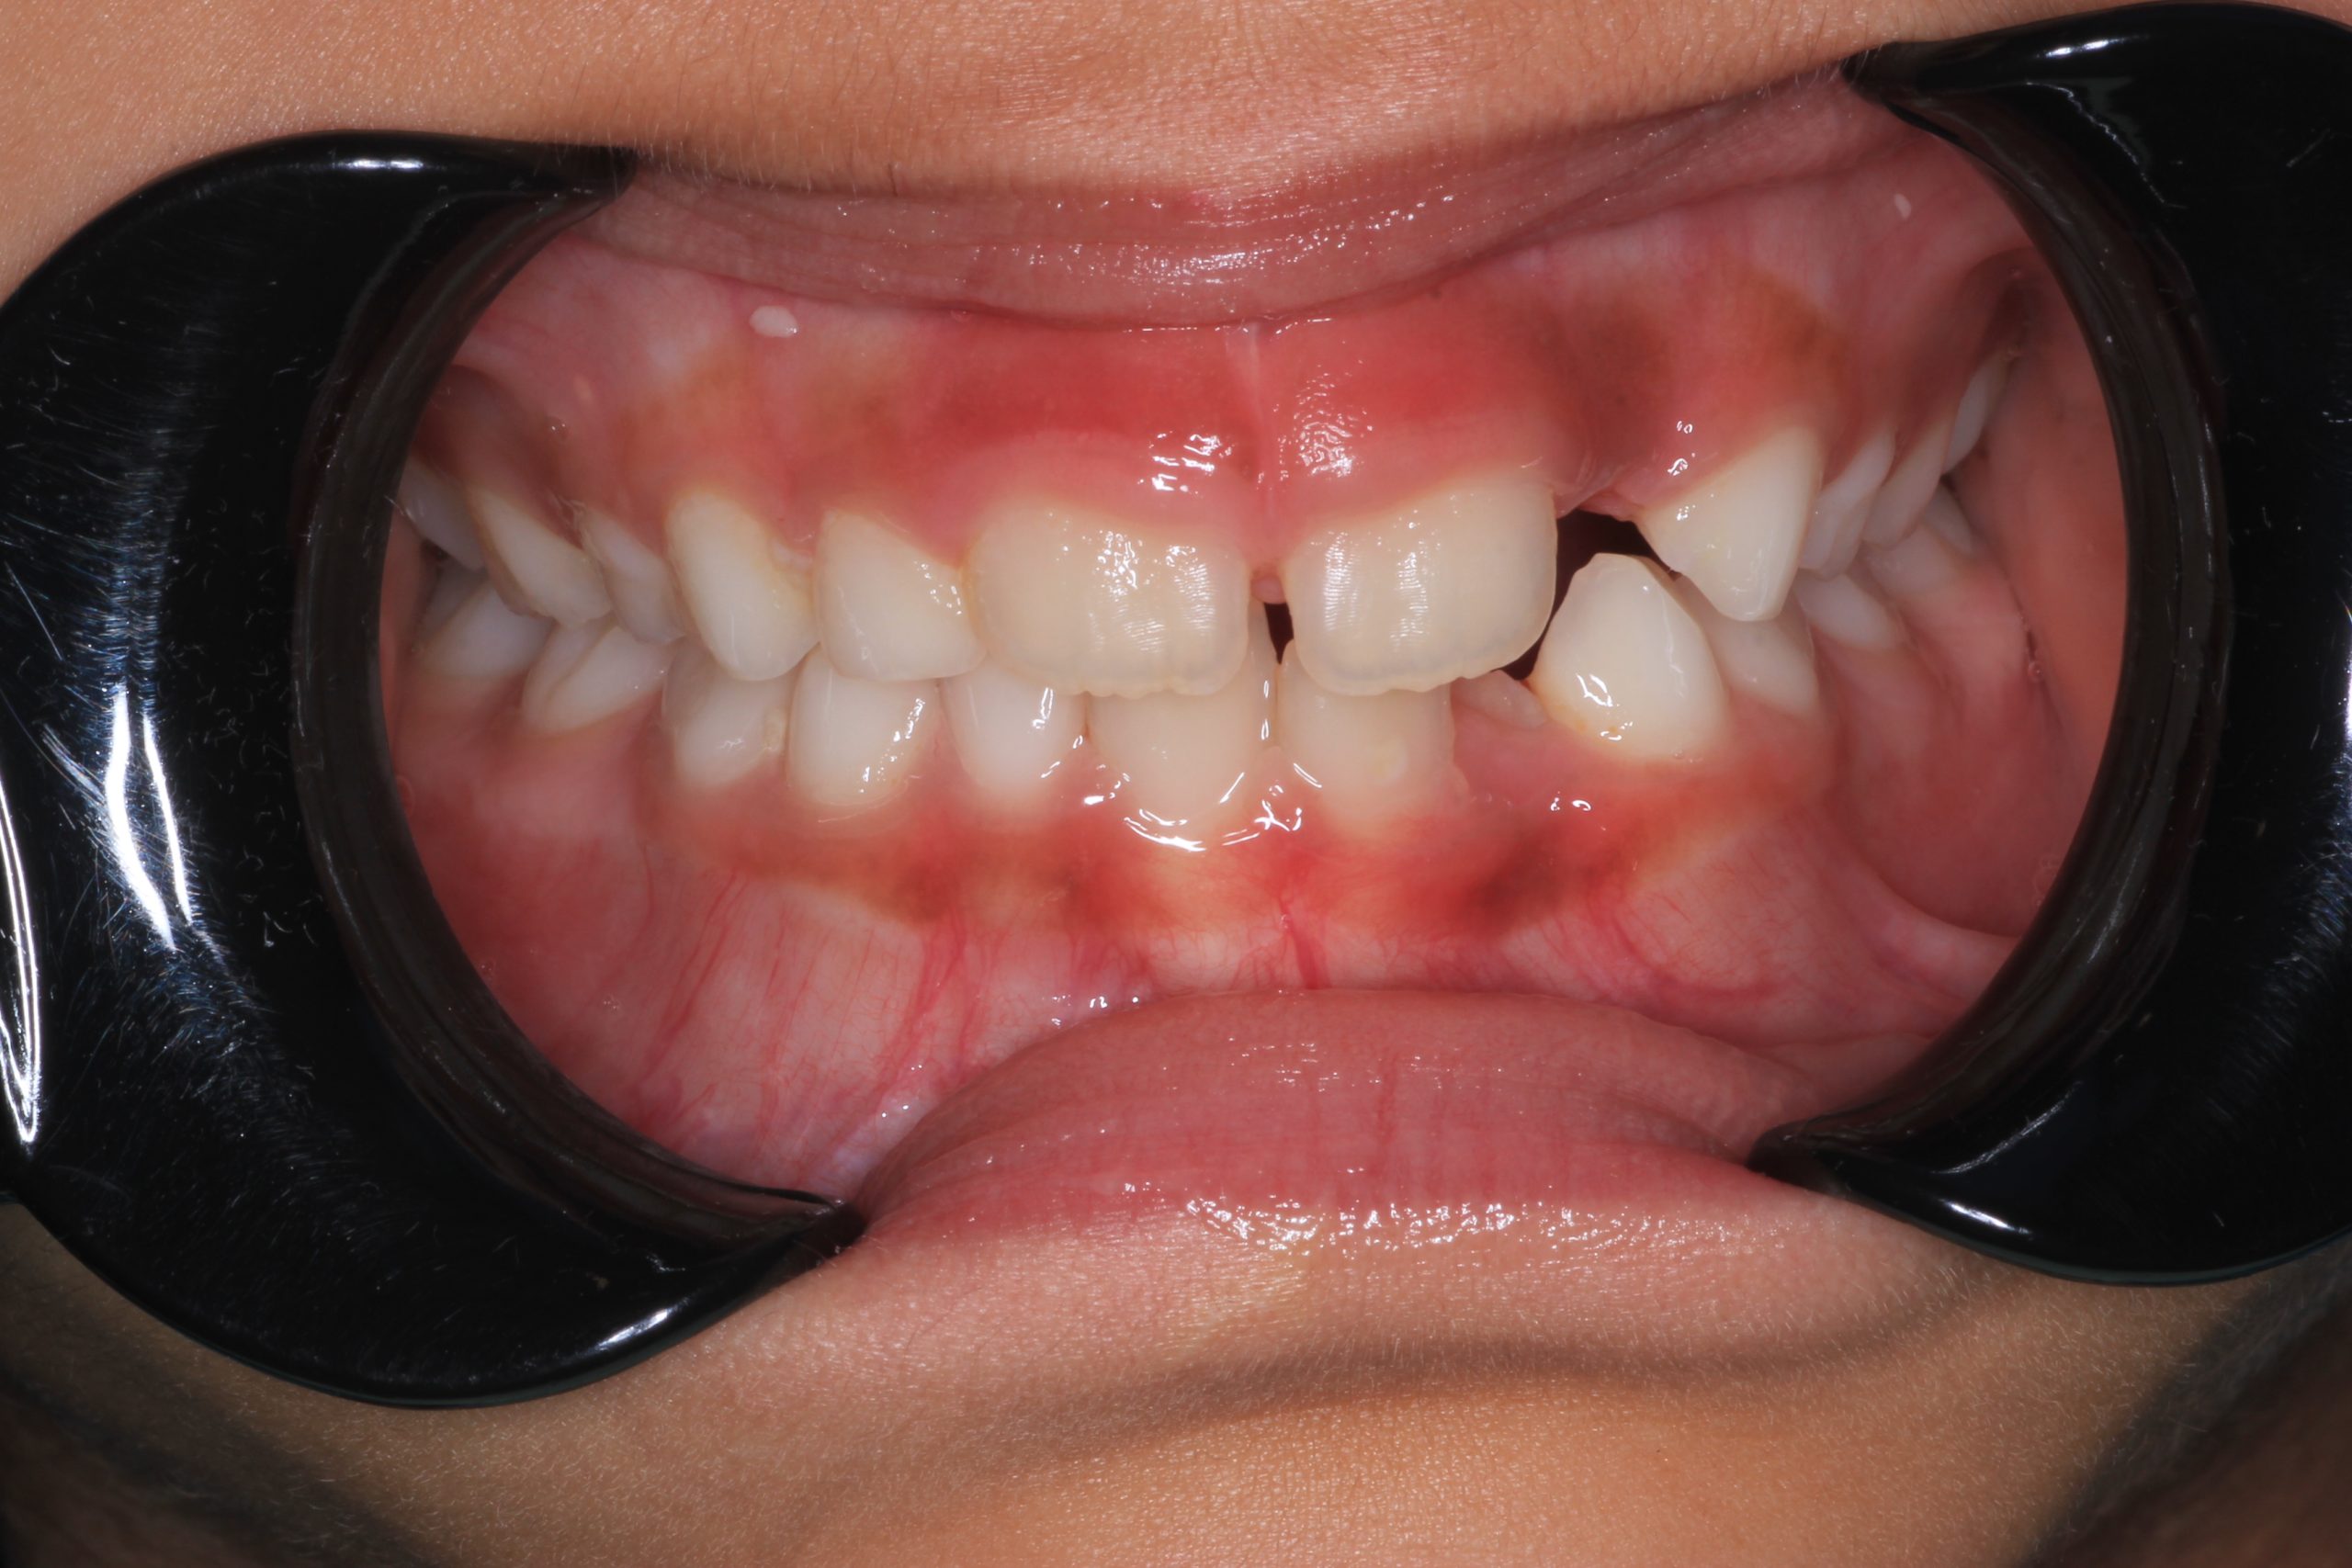

We examine the condition of teeth, gums, and bite. - Plaque Disclosure with Special Indicators

Areas that weren’t cleaned well appear purple. The darker the shade, the older the plaque. This helps both kids and parents understand where brushing needs to improve. - Brushing Training & Home Care Tools Selection